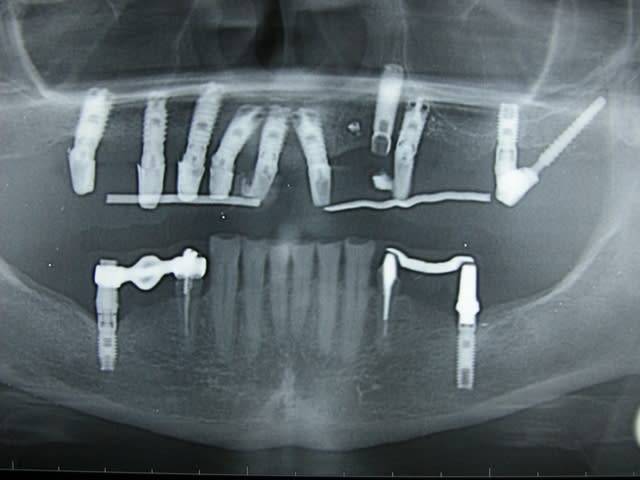

Tu l'as dit :

Implant  k och uk tyjlwf - Eugenol

Photo pluton1b h9n4ea - Eugenol

si j'ai bien compté....y en a 40...là c'est sûr çà doit tenir....ah oui...il aurais pu encore rajouter des clavettes en travers ou des contres écrous....;-))

Non mais, c'est du sérieux ? c'est du photoshop ?

Le patient risque de mourir d'une allergie au titane !

20 mini implants, mise en charge immédiate.

c'est un collègue qui m'a envoyé cela la sem. passée